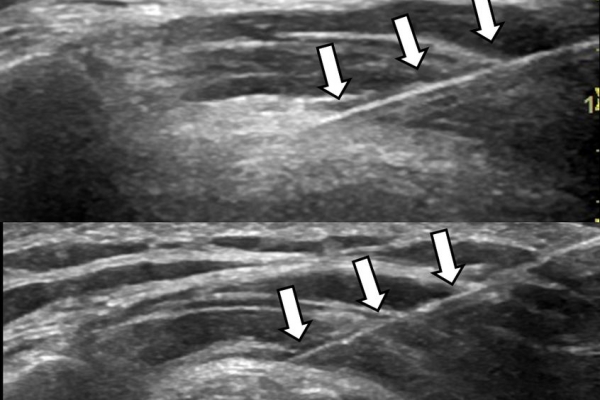

Υπό συνεχή υπερηχογραφική παρακολούθηση είναι δυνατόν να πραγματοποιηθούν κατευθυνόμενες εγχύσεις σε ορθοπαιδικές και ρευματολογικές παθήσεις. Αρχικά εντοπίζεται η παθολογική περιοχή και στη συνέχεια εξετάζεται η βέλτιστη οδός προσπέλασης. Ακολούθως γίνεται υπό άμεση και συνεχή υπερηχογραφική παρακολούθηση οι απαραίτητοι χειρισμοί και έγχυση φαρμάκων ακριβώς στη θέση της βλάβης.

Οι διαγνωστικές-θεραπευτικές εγχύσεις είναι δυνατόν να γίνουν σε μια πλειάδα μυοσκελετικών-ρευματολογικών παθήσεων όπως: